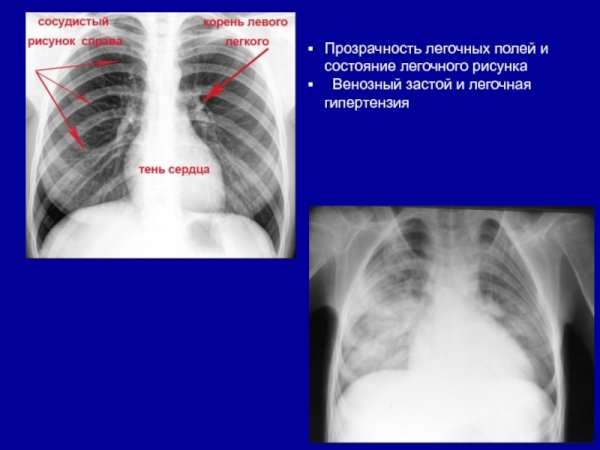

Усиление сосудистого рисунка легких на рентгене - это явление, которое может быть наблюдаемо при проведении рентгенологического исследования органов дыхания. В результате усиления сосудистого рисунка, на снимке становятся более заметными сосуды, расположенные внутри легких. Это может свидетельствовать о различных патологических процессах, таких как воспаление легких, обструкция дыхательных путей или сердечная недостаточность. Усиление сосудистого рисунка является важным признаком для постановки диагноза и выбора оптимального лечения. Однако, для точной интерпретации рентгеновского снимка необходимо учитывать и другие клинические данные, а также провести дополнительные исследования, если необходимо.